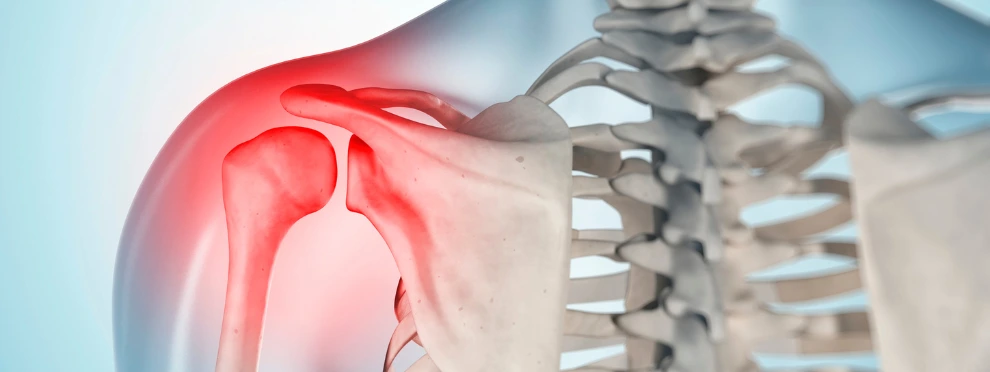

AC JOINT REPAIR in greater noida

Restore Shoulder Stability and Movement with Expert AC Joint Repair

An AC (acromioclavicular) joint injury can cause sharp pain at the top of the shoulder, difficulty lifting the arm, trouble sleeping, and limitations in both work and sports. At Greater Noida Orthopaedic Clinic, Dr. Bharat Goswami provides specialized AC Joint Repair to treat ligament damage, restore proper joint alignment, and bring back smooth, pain-free shoulder motion.

With accurate diagnosis, targeted physiotherapy, image-guided pain relief, and minimally invasive surgical stabilization when required, patients experience long-lasting pain relief and regain full confidence in shoulder strength and performance.

AC joint injuries occur when the ligaments connecting the collarbone to the shoulder become stretched or torn. Advanced treatment helps realign the joint, support healing, and restore full shoulder function for active living.